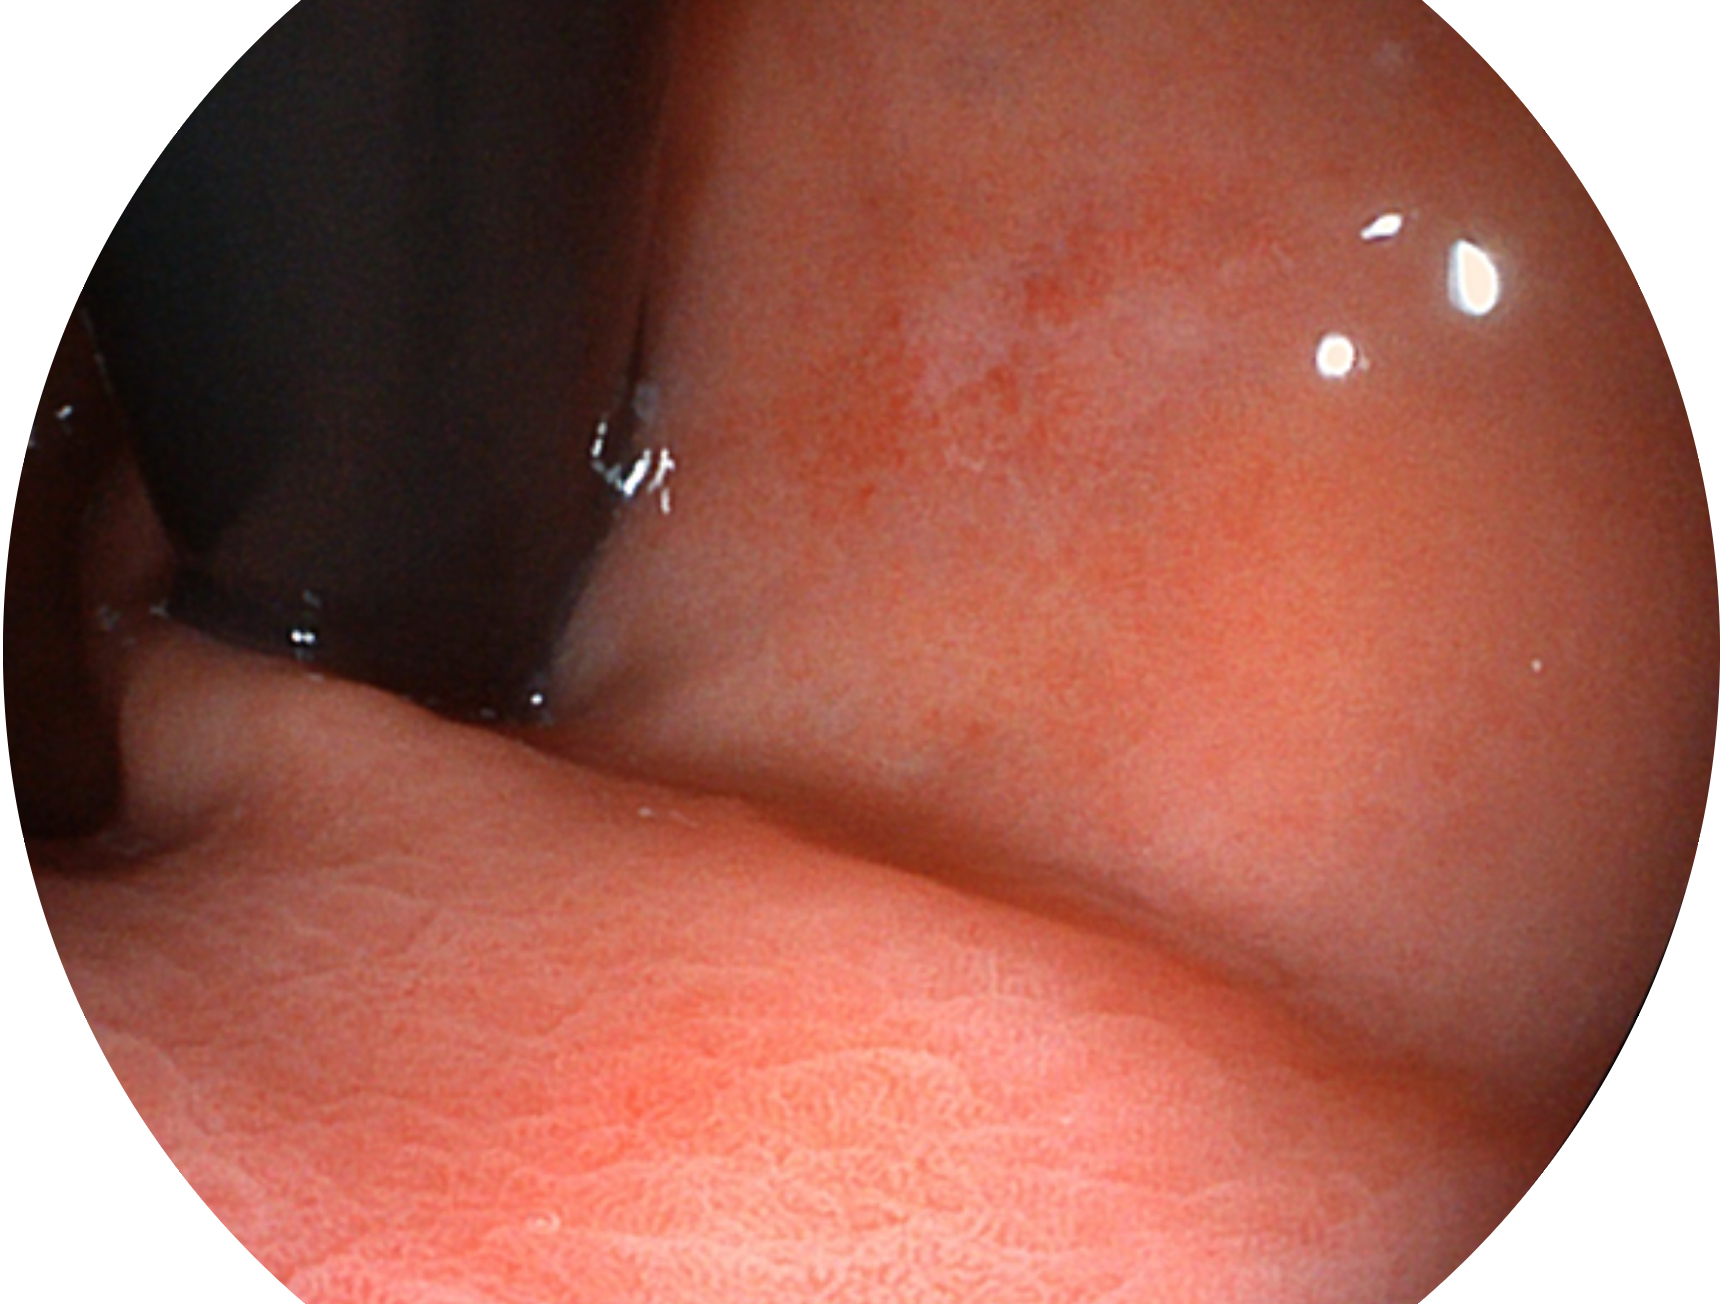

与上一代VIST相比,摒弃了滤光转轮而直接采用光谱组合的方案,加入了血红蛋白吸收高峰与次高峰的蓝紫光和绿光光谱,更有利于黏膜血管吸收,突显浅表层血管和中层血管的对比度,因而具备更高的图像对比度,近景观察时,有助于微细结构变化及病灶边界的观察。

• 白光图像 VIST图像